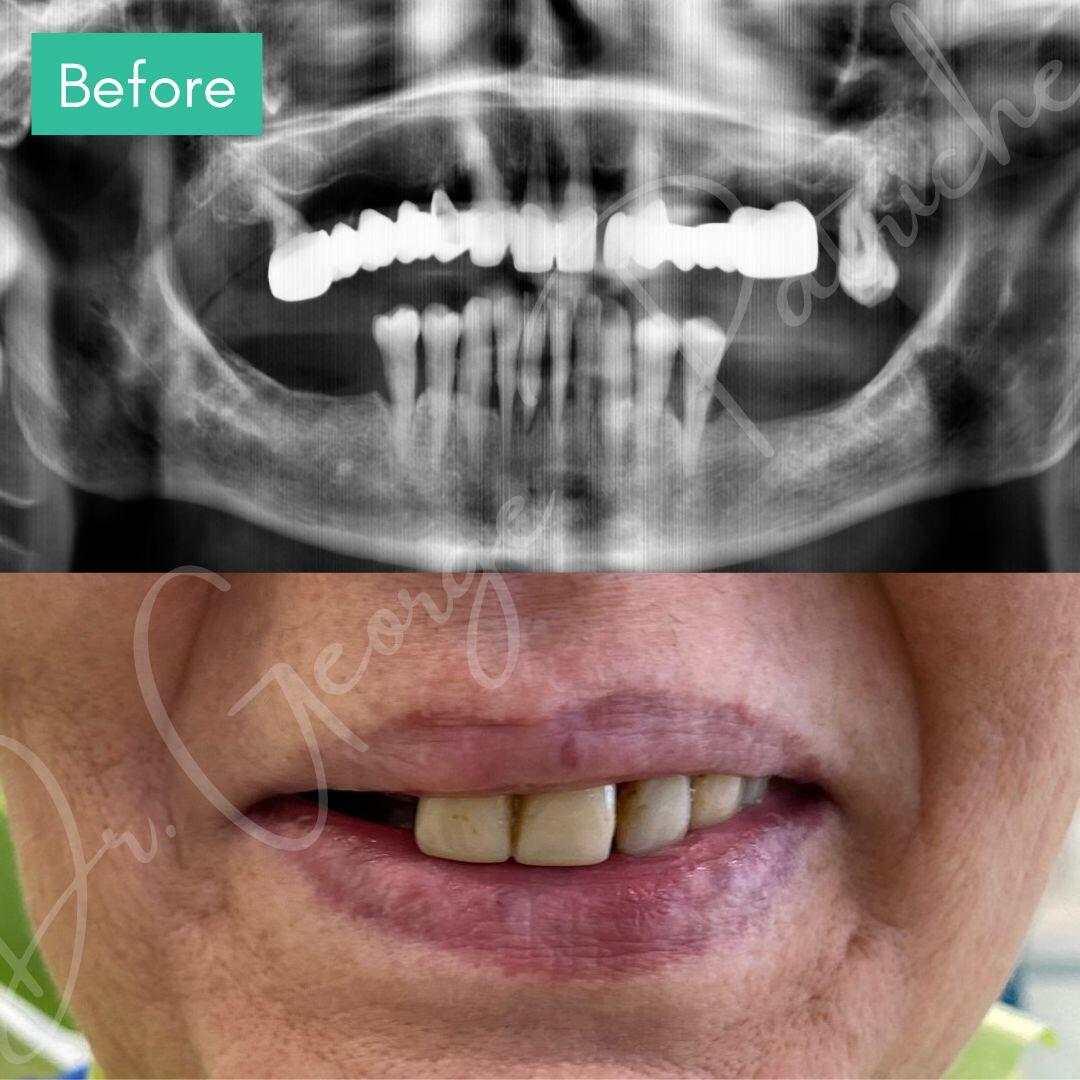

Before & After